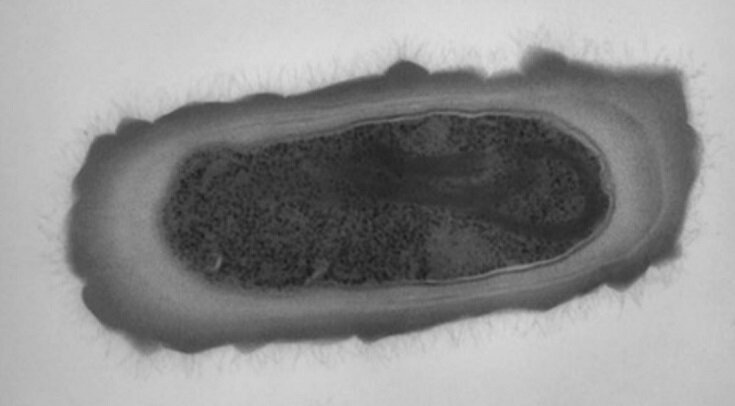

Marco Baloh et al. / Journal of Bacteriology, 2017

Кишечные инфекции, вызванные антибиотикорезистентной бактерий Clostridioides difficile, ежегодно уносят сотни тысяч жизней. Даже если использовать многокомпонентную агрессивную терапию антибиотиками последних поколений, инфекция в большинстве случаев рецидивирует.